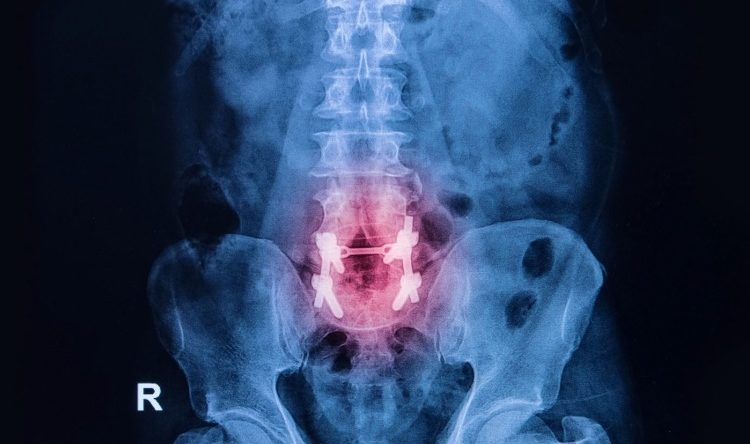

Resolution of Low Back & Pelvic Pain in a Pregnant Patient Utilizing the Webster Technique: A Case Report & Review of the…